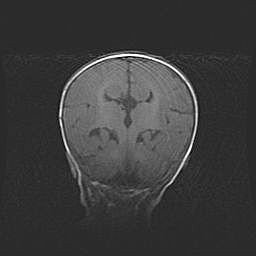

Открытая гидроцефалия.

Возраст: 6 месяцев 15 дней

Вес: 6200 г

Пол: женский

Окружность головы: 41 см

Срок гестации: 38 недель

Гидроцефалия головного мозга у новорожденных – это скопление избыточного количества цереброспинальной жидкости в головном мозге. Ее избыточное скопление в мозге приводит к патологическому расширению желудочков мозга (четырех полостей, расположенных в глубине белого вещества мозга, заполненных цереброспинальной жидкостью и связанных узкими проходами).

Открытый тип гидроцефалии (сообщающаяся) наблюдается тогда, когда нарушен механизм всасывания ликвора в системный кровоток. При этом типе причиной заболевания чаще всего является перенесенные ранее инфекции (например: менингит),  либо же наличие крови в субарахноидальном пространстве.